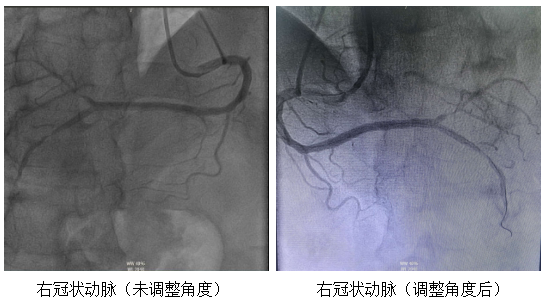

团队创新性地调整了DSA大型C形臂的投照角度,模拟特殊的“俯位”投射。通过让机臂围绕患者进行一系列适配性角度的投照,从特定方向采集图像,从而在源头上获取更易于解读的原始影像。这一调整使医生能够运用最熟悉的解剖思维进行手术,显著缩短了术中判断与操作的时间。

病变精准显影:得益于设备特殊投照与影像反转技术,患者的冠状动脉树在屏幕上清晰、直观地展开。造影结果显示,其前降支的走形与空间分布与正常人完全一致,但近段存在重度狭窄。

支架“镜像”输送与释放:在指引导管的支撑下,术者沿导丝将支架送至病变处。最终,支架被精准定位并成功释放,术后造影及血管内超声(IVUS)证实,支架贴壁良好,血流恢复畅通。